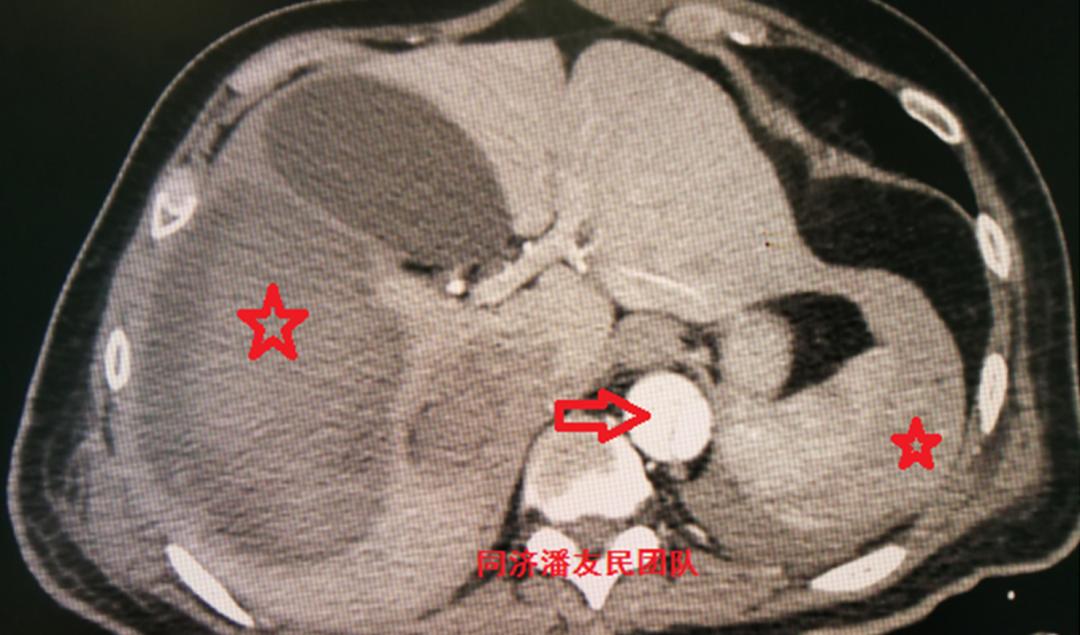

入院后,胸腹主动脉CTA将主动脉及胸腹腔脏器一起进行全面评估。与图1平扫CT层面对应,图2显示降主动脉夹层。

红星号显示纵隔血肿,白箭头显示胸腔积液。

CTA同时发现脾脏破裂出血合并腹腔积液(图3)。